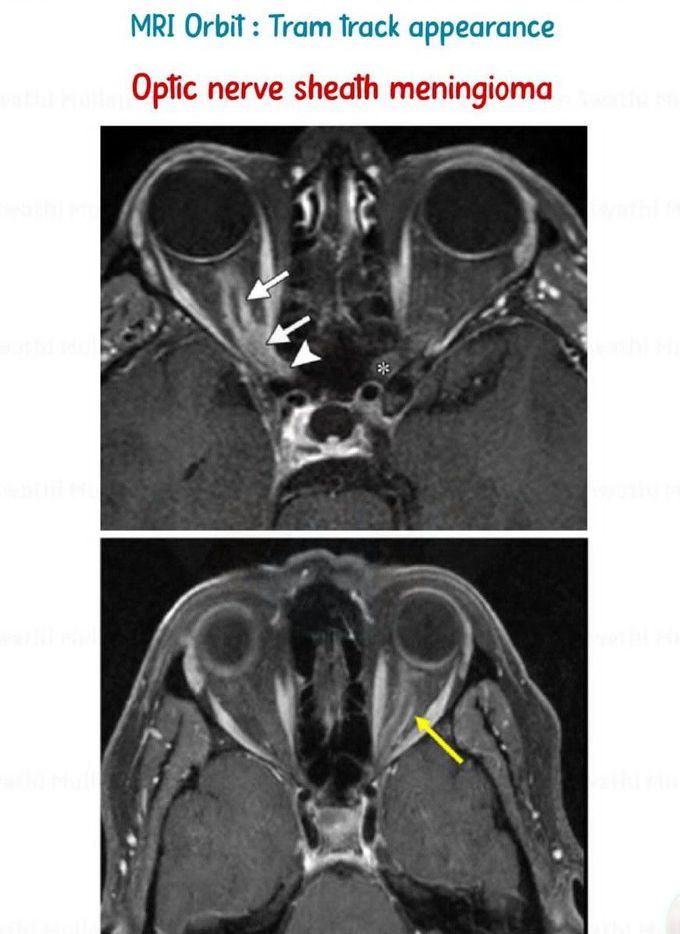

Tram Track Appearance I

Tram track appearances or tram track signs are medical signs that bear some resemblance to tramway tracks. They are seen in different conditions